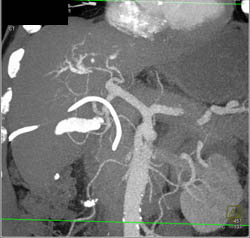

Cholangiocarcinoma